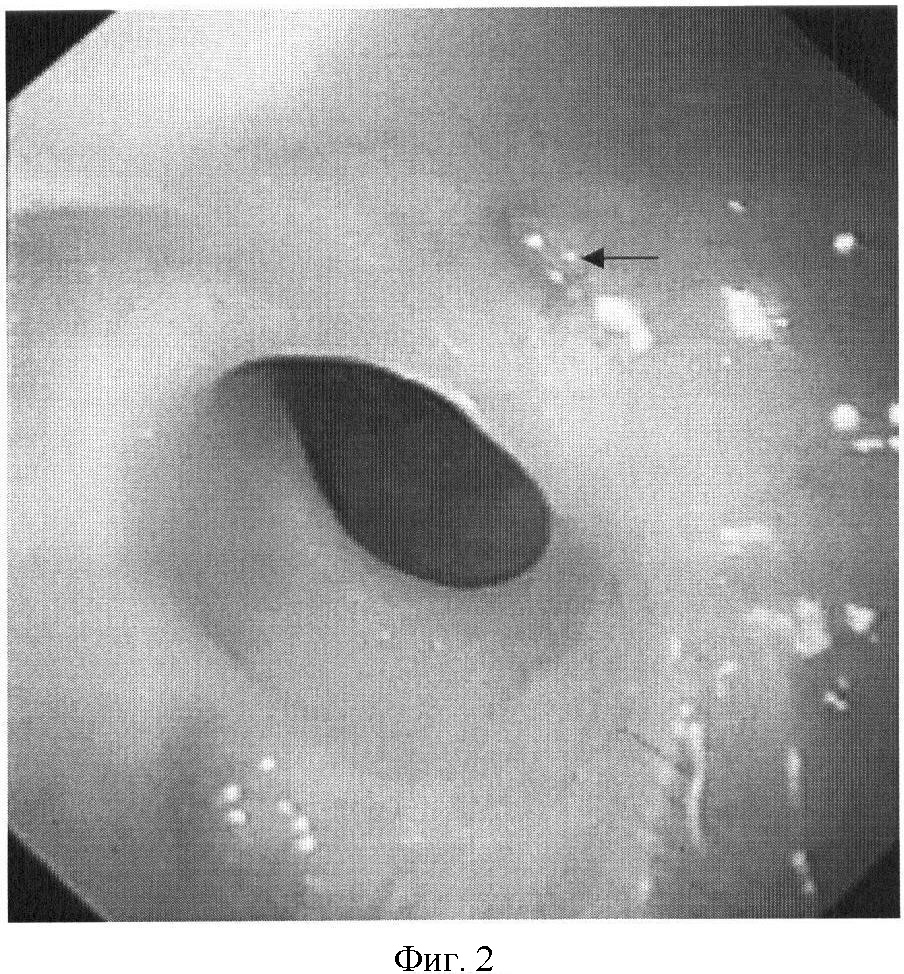

На фиг.1 представлена рентгенограмма пищевода с контрастным веществом: определяется контрастирование трахеопищеводного свища. На фиг.2 представлена эндоскопическая картина просвета пищевода: устье трахеопищеводного свища указано стрелкой. На фиг.3 представлена эндоскопическая картина просвета пищевода: предварительно в устье трахеопищеводного свища, открывающегося в просвете трахеи, было ведено 0,8 мл красящего вещества (метиленовой сини), после этого в просвете пищевода определяется прокрашивание устья трахеопищеводного свища (указано стрелкой). На фиг.4 – пломбирование устья трахеопищеводного свища тахокомбом, предварительно устье свища было последовательно подвергнуто электрокоагуляции и химиокоагуляции (96% этиловый спирт). На фиг.5 – клиппирование запломбированного устья свища. На фиг.6 – контрольная эзофагоскопия, выполненная через 3 месяца после операции: в просвете пищевода в области устья трахеопищеводного свища определяются две скрепки. На фиг.7 – контрольная рентгенограмма после эндоскопического лечения (через 3 месяца): в области трахеопищеводного свища определяется незначительный дефект наполнения (указан стрелкой), трахеопищеводный свищ не контрастируется.

фиброэзофагоскопия – на 16 см от края зубов по правой стенке пищевода определяется свищ, устье диаметром 0,3 см;